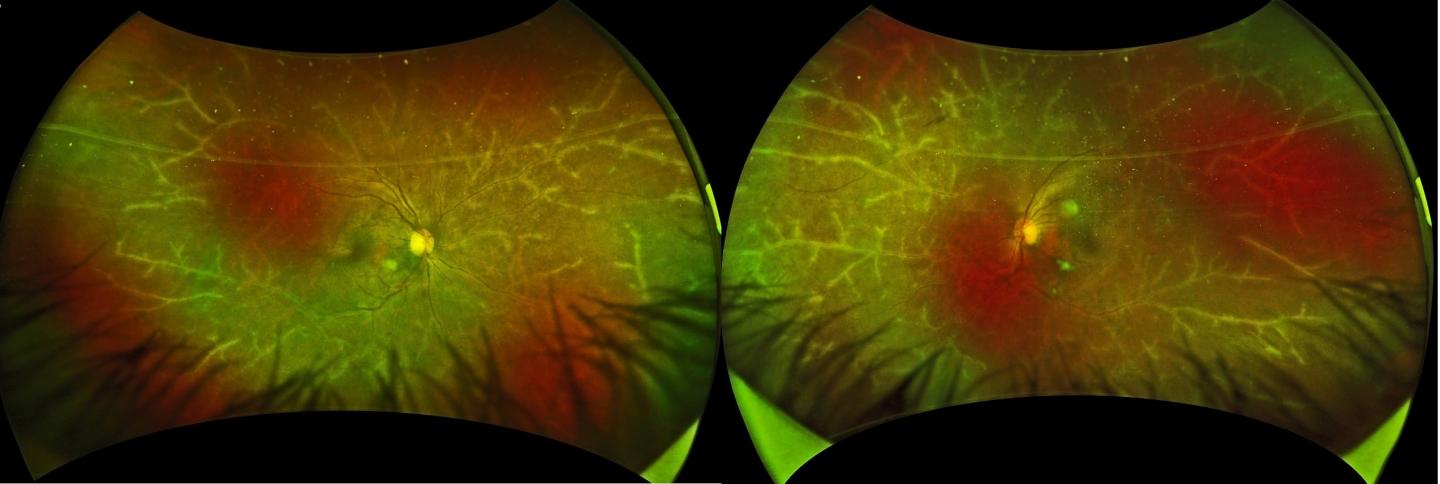

image: Widefield imaging of frosted branch angiitis.

Over four years after HSCT, she developed blurred vision and was referred for further examination. A slit-lamp biomicroscope, which shines a thin sheet of light into the eye for inspection, revealed cellular infiltrates in both segments. Associate Professor Koju Kamoi, lead / corresponding author, describes the remarkably picturesque fundoscopy findings. "Along the retinal blood vessels, a translucent sheath was visible resembling the icy branches of a tree in winter. We recognized this as frosted branch angiitis (Figure A), a rare presentation of florid retinal vasculitis."